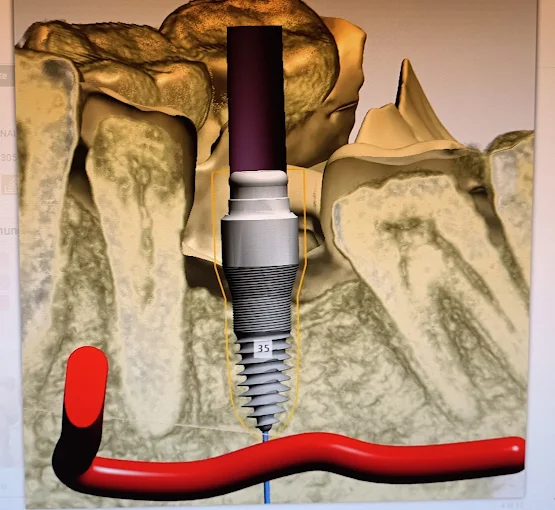

Zahnimplantate aus deutscher und schweizer Herstellung mit bis zu 98% Erfolgsquote, auch ohne Knochenaufbau möglich.